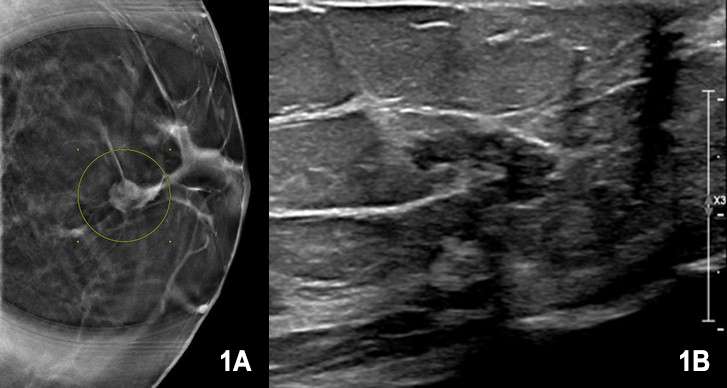

Case: Papillary Carcinoma Figure 1

Figure 1A , 1B. 71-year-old female presents for callback from screening. Mammography showed a well circumscribed mass measuring approximately 14 mm in the left breast. Targeted sonography demonstrated an irregular, hypoechoic mass with indistinct margins measuring 14 mm x 7 mm x 7 mm at 12 o’clock, 2 centimeters from the nipple. A biopsy was performed which showed an atypical papillary lesion, favored to be low grade solid papillary carcinoma. Patient subsequently underwent wire localized lumpectomy at an outside hospital with the final diagnosis determined to be low grade solid papillary carcinoma without evidence of invasive carcinoma.